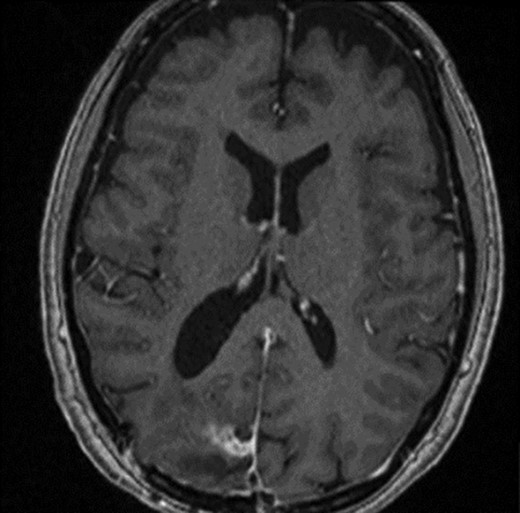

Two weeks later, whilst awaiting surgery, she attended the Emergency Department with a fever of 38.6°C and mildly raised inflammatory markers (WCC 10.4, Neut 8.4). Urine dip and CXR were unremarkable. The source of the infection was not isolated and the emergency medicine physicians discharged her with a course of empirical oral antibiotics. The neurosurgical team were not made aware of this attendance. Twelve days later, she underwent a planned neuronavigation-planning MRI scan as an outpatient. This was arranged one week prior to the scheduled surgery, in line with our departmental protocol. The MRI was reviewed and two new rim-enhancing collections superior and inferior to the tumour were noted, associated with extensive perilesional oedema (Fig. 2A and B). The patient was then immediately contacted via telephone and reported new worsening of headaches and new right sided weakness. She was admitted to hospital directly for assessment and emergency treatment. Her inflammatory markers on admission had risen to a WCC of 19.5, Neut 16.6, but CRP was <1. She was started on an emergency steroid treatment and subsequently underwent craniotomy, total resection of the meningioma and drainage of the intraparenchymal paratumoural abscesses. Intra-operatively the brain was swollen; pus collections were encountered in abscess cavities superior and inferior to the solid tumour, which had a necroticcore.

T1 weighted MRI postgadolinium enhancement in both sagittal (A) and coronal (B) views. There are two new rim-enhancing cystic lesions. A superior lesion of 31.4 mm as measured on the coronal reconstructed images and is abutting the adjacent dura of the right parietal lobe and is sited superior and lateral to the right occipital lesion. Another lesion sited inferior to the known right occipital lesion is the larger of the two lesions and has a septation within it. This measures approximately 34.4 mm on the coronal reconstructed images. On the sagittal images, it can be seen that the anterosuperior enhancing border of this lesion has a thicker and more ill-defined age. There is an adjacent vasogenic oedema.